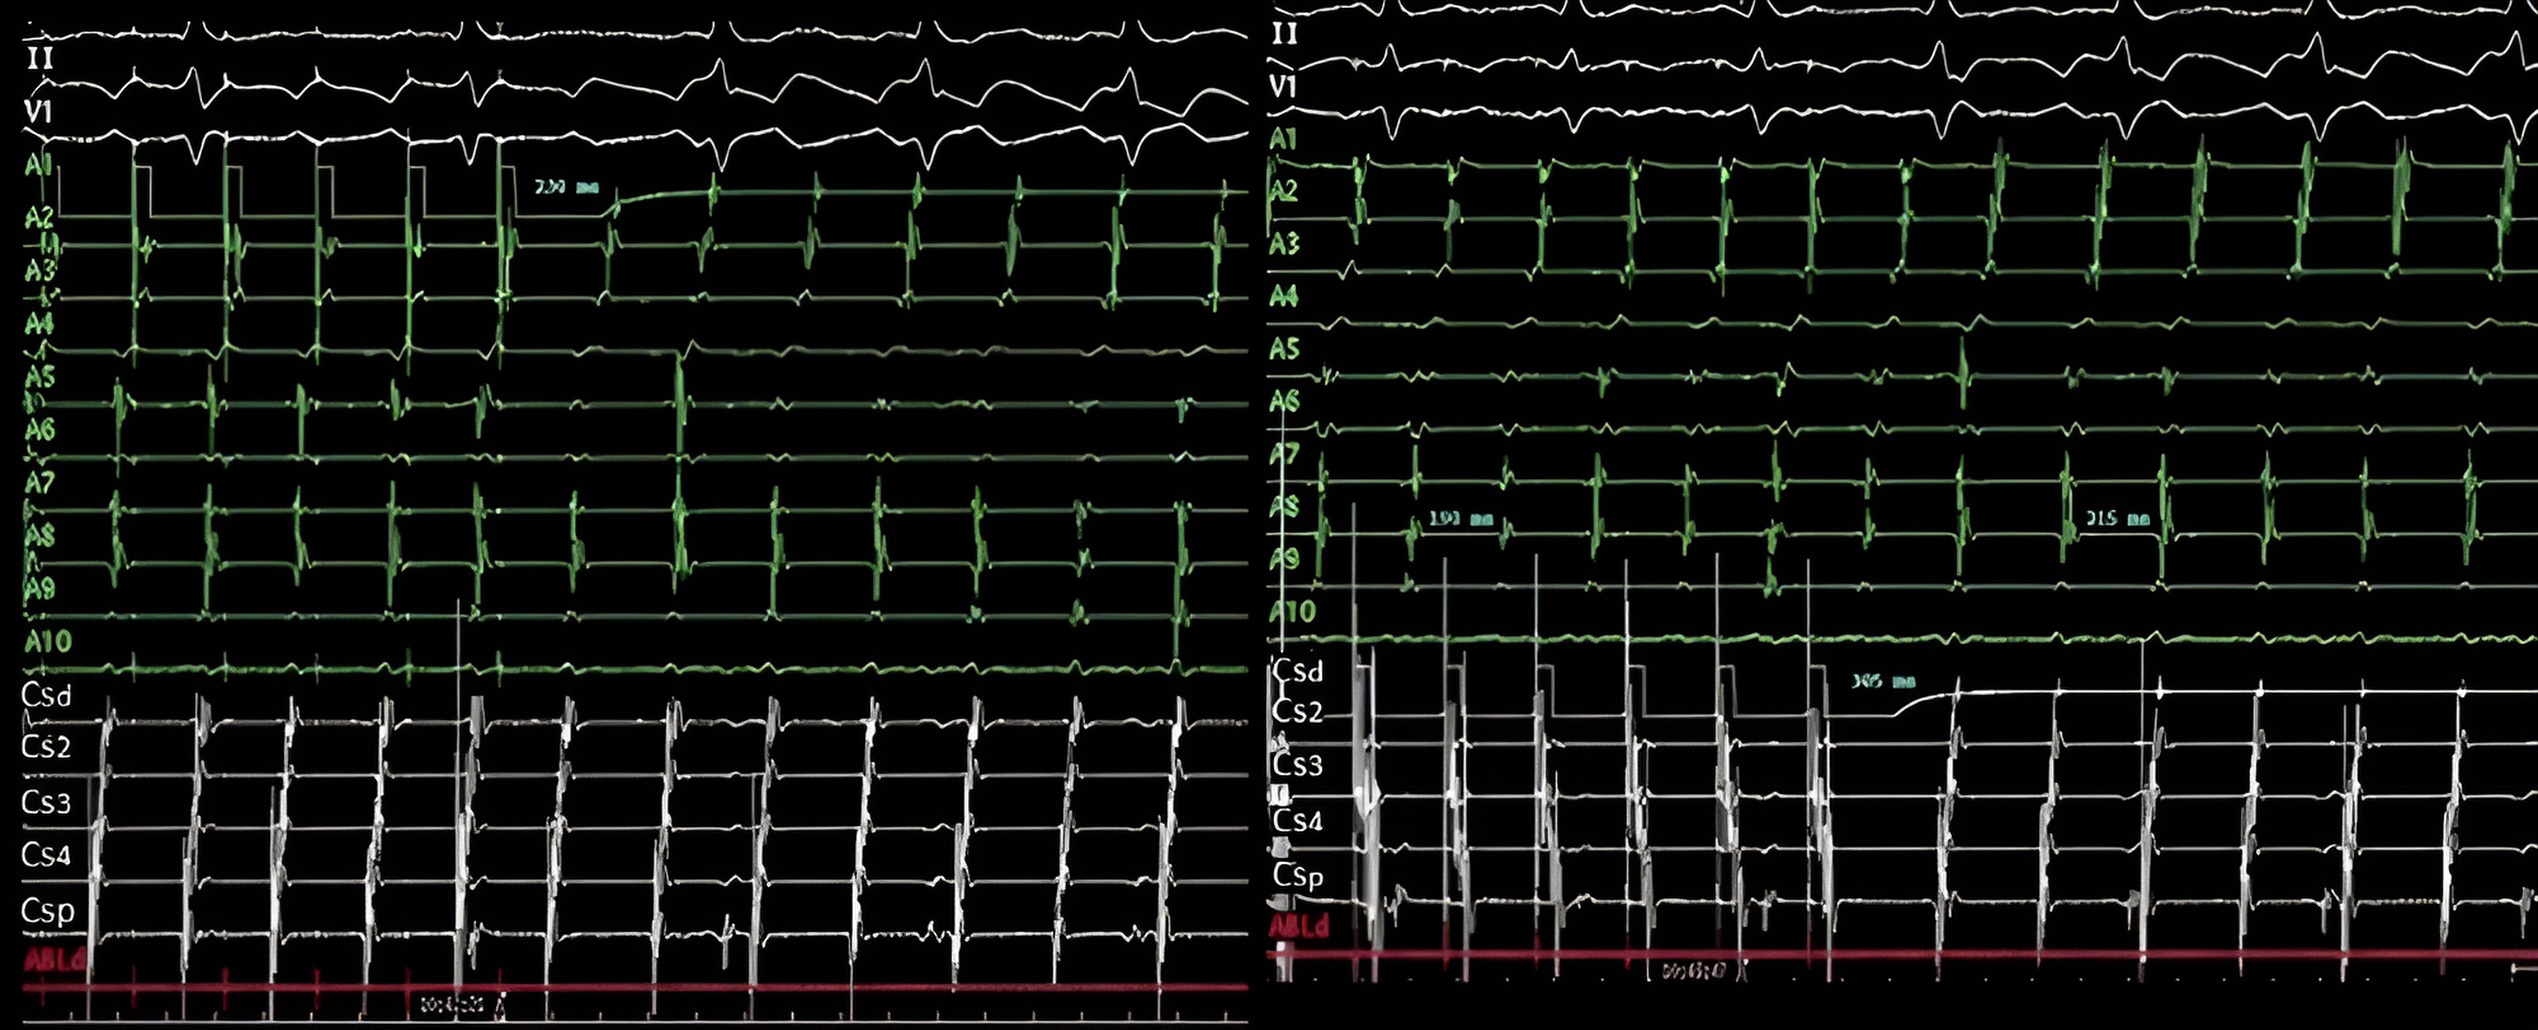

Fig. 1.Counterclockwise typical flutter activation. Left: 1-2 to 19-20 represents the 10 dipoles from a 20-poles catheter placed in the right atrium close the tricuspid valve. Prox 9-10 to Dist 1-2 represents the 5 dipoles from a 10-poles catheter inserted into coronary sinus, around mitral annulus. Yellow arrows show wavefront propagating through the interatrial septum, right atrium roof, and lateral wall of the right atrium before returning to the cavotricuspid isthmus (CTI) with the slow conduction zone. Left atrium is activated passively from this wavefront crossing interatrial septum in a caudocraneal sense. Right: Electrophysiological tracings from these catheters. A1–A10 represents the bipolar recordings of the 20-poles catheter displaying consecutive, sequential activation from A10 to A1, followed by the electrogram recorded by the ablation catheter (ABLd) located in the CTI. From there, the activation spreads both toward the left atrium, electrograms registered by coronary sinus (CS) catheter, CSd to CSp, and ascending again through the septum (A10). CTI, cavotricuspid isthmus; His, His bundle; Prox, proximal; Med, medium; Dist, distal; ABLd, distal ablation catheter; CSd, distal coronary sinus; CSp, proximal coronary sinus.

Fig. 2.Reverse typical flutter. The arrangement of the catheters, bipoles and recordings is the same than in Fig. 1. (Left) Scheme illustrating how the activation front in this case moves in a clockwise direction, propagating through the anterolateral wall of the right atrium in a caudocranial direction before reaching the septal wall in a craniocaudal direction. (Right) Right atrium electrograms shows the clockwise sequence, starting at A1, low anterolateral wall, and propagating along contiguous dipoles toward right atrium roof (pairs 7-8 to 11-12), septum and cavotricuspid isthmus (CTI) where the ablation catheter (ABL) is placed. His, His bundle; Prox, proximal; Med, medium; Dist, distal; CS, coronary sinus.